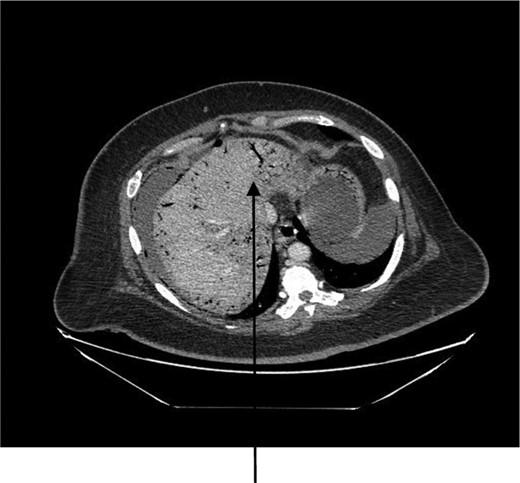

A 44-year-old female presented to the emergency department with generalized abdominal pain that became suddenly severe and diffuse 5 hours before presentation. She described the pain as sharp, alleviated by lying still on her back and worsened by moving. Pain radiated to her back. She also had watery non-bloody diarrhea that started 2 weeks before presentation. She had a medical history of poorly controlled type 1 diabetic mellitus and hypertension. No history of STDs or IUD use. Some of her labs on presentation were as follows: WBC 7.400/mm3, hemoglobin 15.6 g/dl and blood glucose 249 mg/dl. On examination, we found a hypotensive, dehydrated, obese female in septic shock with a tense, massively distended abdomen, which was diffusely tender. CT of the abdomen and the pelvis revealed pneumoperitoneum, a large right abdomino-pelvic mass measuring 17.6 × 12.1 × 20 cm, that appeared to be a septic ovarian cyst (Fig. 1) and diffuse portal venous gas throughout the liver (Fig. 2). Resuscitation and rehydration were initiated, and broad-spectrum intravenous antibiotics were administered. Hemodynamic instability continued, and she was emergently taken to the operating room for an exploratory laparotomy. Upon opening the abdomen pneumoperitoneum and diffuse purulent peritonitis was obvious. There was bullous emphysema of the wall of the uterus. The gallbladder had been previously removed. The stomach, duodenum, small bowel, appendix and colon were normal and involved only by serositis from the purulent peritonitis. A pus-filled right ovarian cyst, subscapular gas bubbles over the liver and a cecal bascule were the dominant abnormalities. A right salpingo-oophorectomy, appendectomy and peritoneal lavage with 15 liters saline and antibiotics were accomplished. She received a total of 7 liters of intravenous crystalloid resuscitation intraoperatively and 2 units of packed red cell transfusion. The patient was transferred to the surgical intensive care unit (SICU) after the procedure to continue resuscitation and critical care therapy for ongoing septic shock. The patient made a complete recovery and was discharged after a total of 11 days in SICU and 23 days in the hospital ward.

CT abdomen showing large air-filled right abdominal mass that appears to be a septic ovarian cyst.